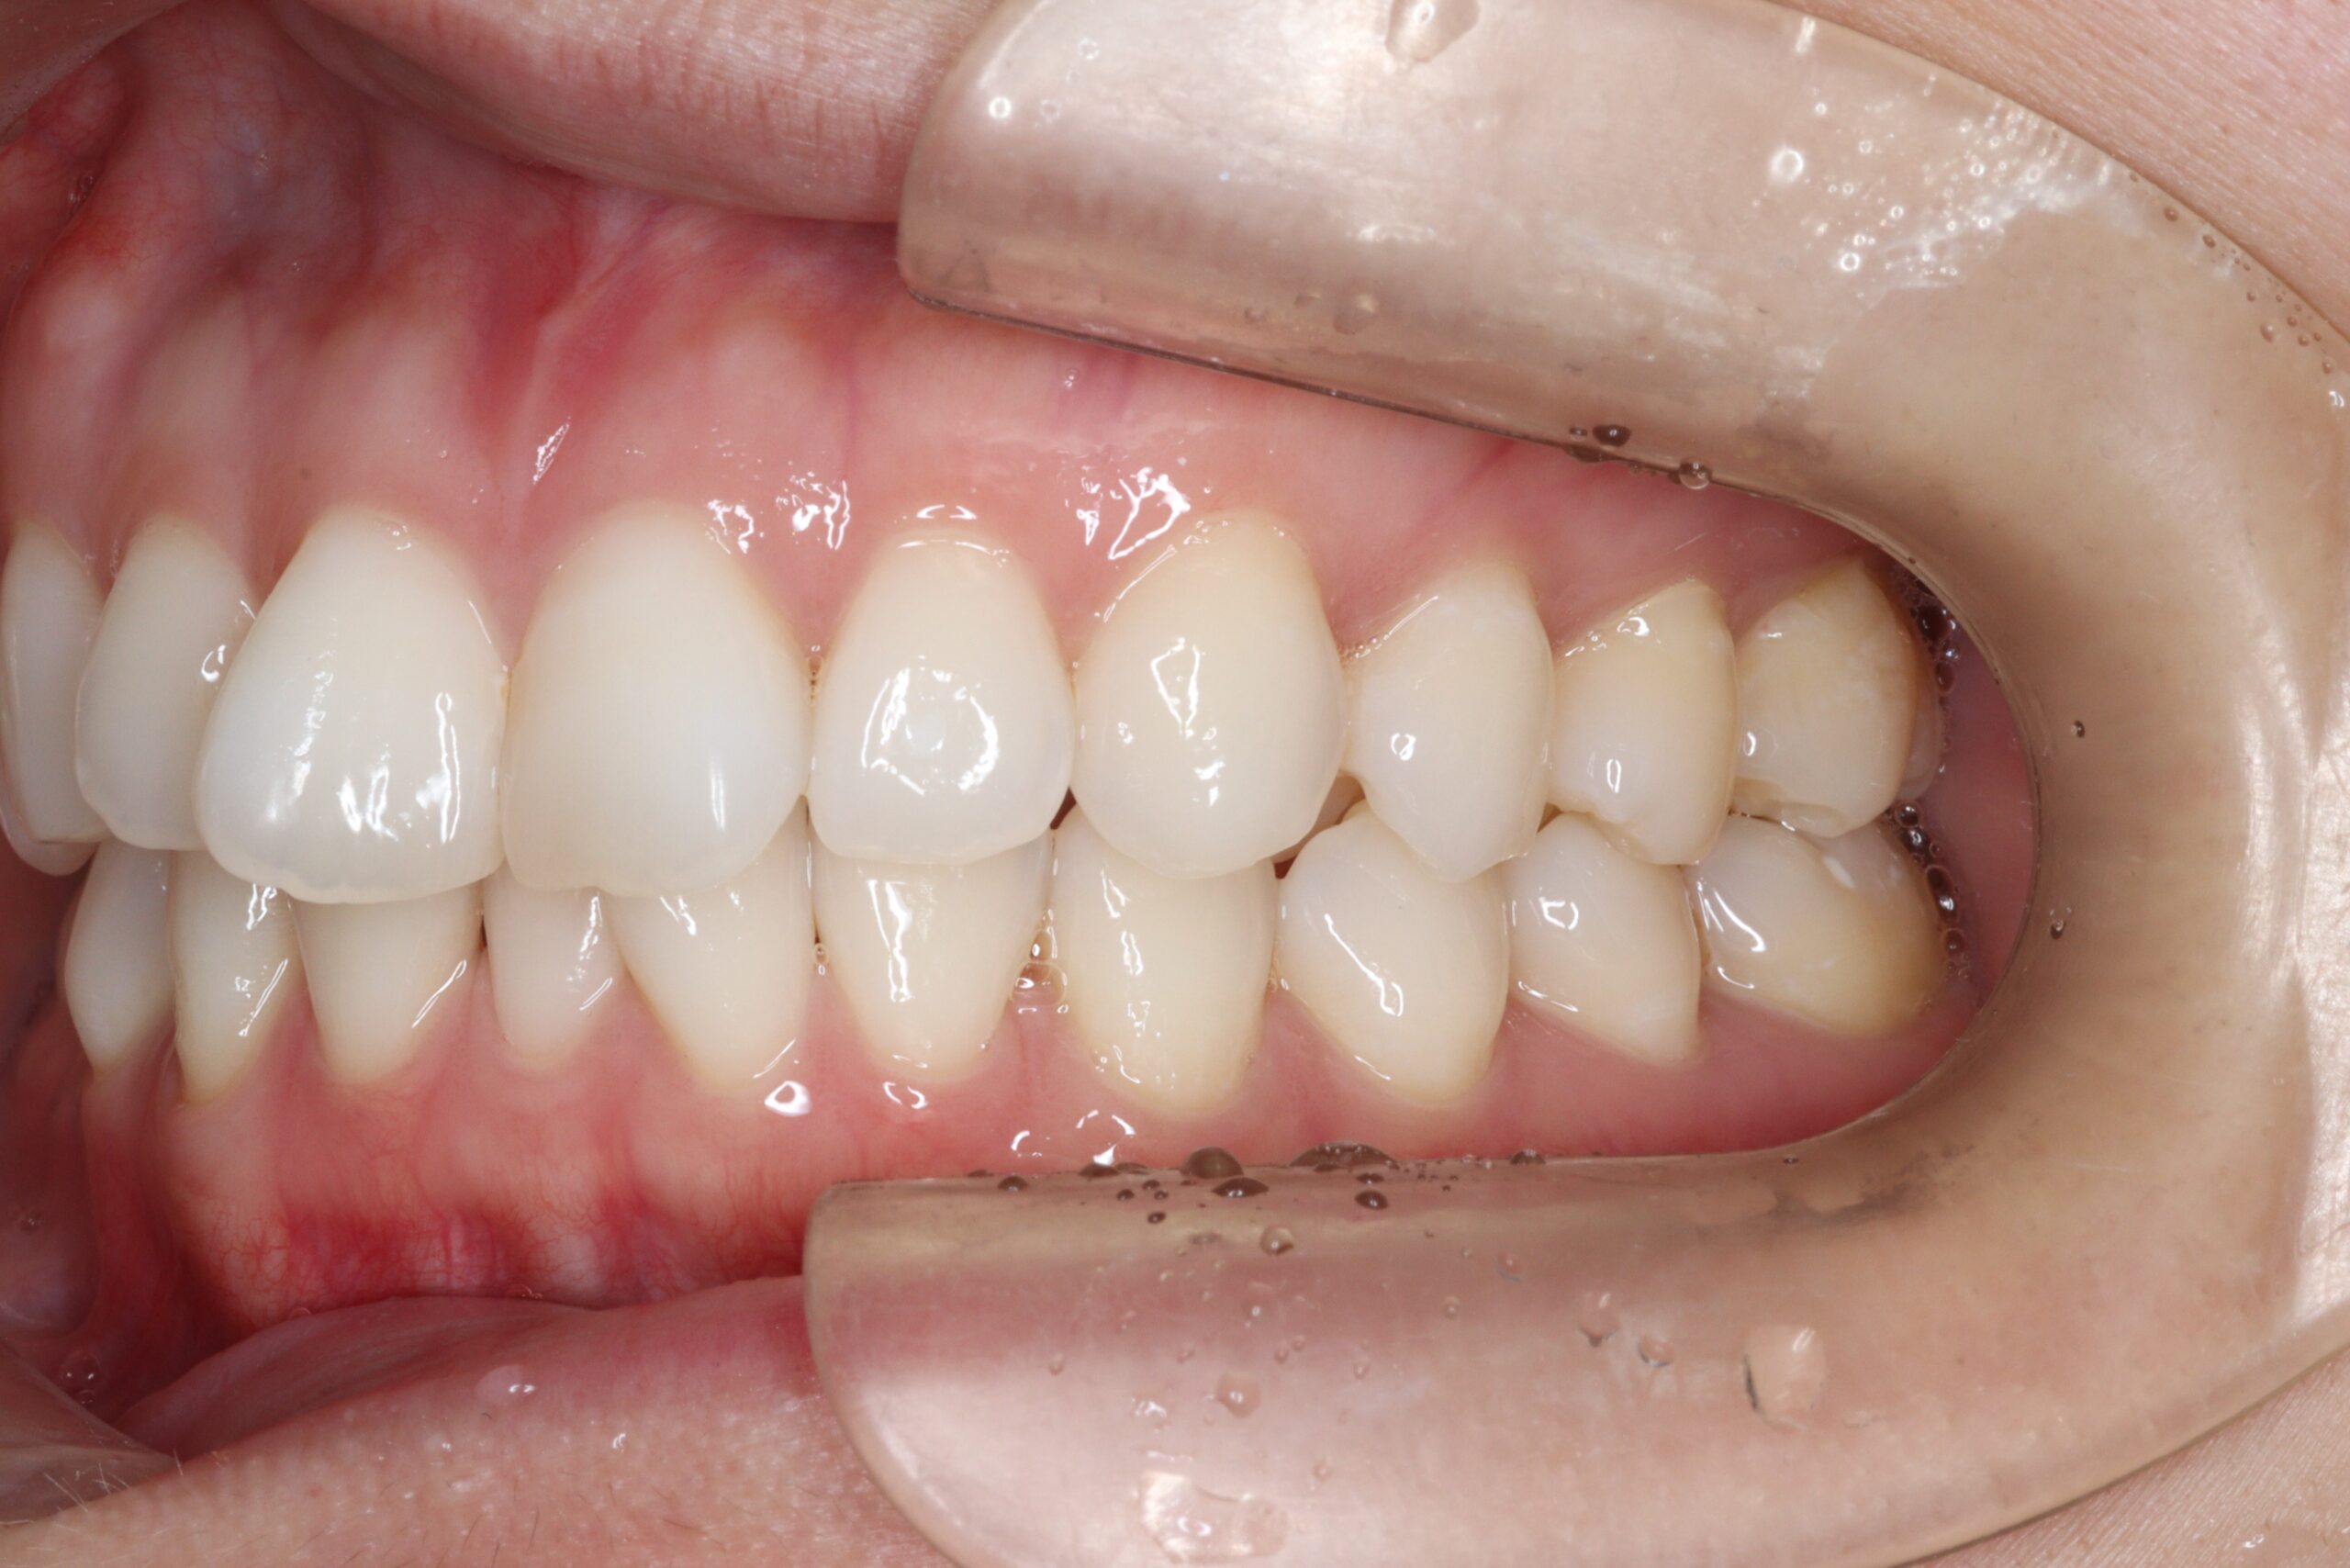

矯正術前:右側

矯正術後:右側